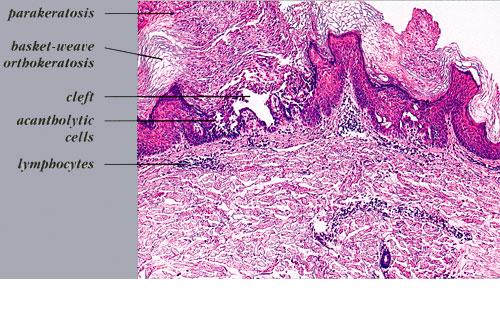

The characteristic changes in Darier’s disease include the following: (a) a peculiar form of dyskeratosis resulting in the formation of corps ronds and grains; (b) suprabasal acantholysis leading to the formation of suprabasal clefts or lacunae; and (c) irregular upward proliferation into the lacunae of papillae lined with a single layer of basal cells, so-called villi (Fig. 6-27). There are also papillomatosis, acanthosis, and hyperkeratosis. The dermis shows a chronic inflammatory infiltrate. In some cases, there is downward proliferation of epidermal cells into the dermis.

The corps ronds occur in the upper stratum malpighii, particularly in the granular and horny layers; grains are found in the horny layer and as acantholytic cells within the lacunae. Corps ronds possess a central homogeneous, basophilic,

pyknotic nucleus that is surrounded by a clear halo. By virtue of size and the conspicuous halo, corps ronds stand out clearly . Peripheral to the halo lies basophilic dyskeratotic material as a shell . The nonstaining halo in some instances is partially replaced by homogeneous, eosinophilic dyskeratotic material . Compared with the corps ronds, the grains are much less conspicuous. They resemble parakeratotic cells but are somewhat larger. The nuclei of grains are elongated and often grain shaped and are surrounded by homogeneous dyskeratotic material that usually stains basophilic but may stain eosinophilic. The lacunae represent small, slitlike intraepidermal vesicles most commonly located directly above the basal layer. They contain acantholytic cells and show premature partial keratinization. Because of shrinkage, some of them are elongated, and these then appear identical with the grains in the horny layer. The villi projecting into the lacunae may be quite tortuous, so on histologic examination, some of them appear in cross section as rounded dermal structures lined by a solitary row of basal cells .